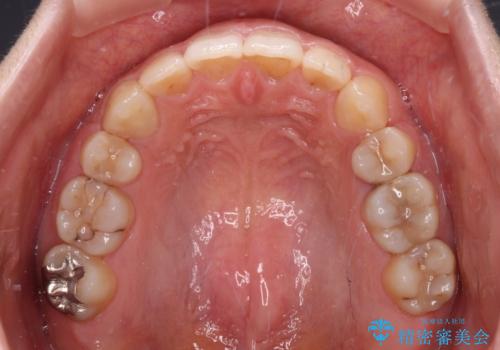

治療は順調に進み、予定された期間で終了することができました。

装置除去後には、スッキリとした口元となり、大変満足していただきました。